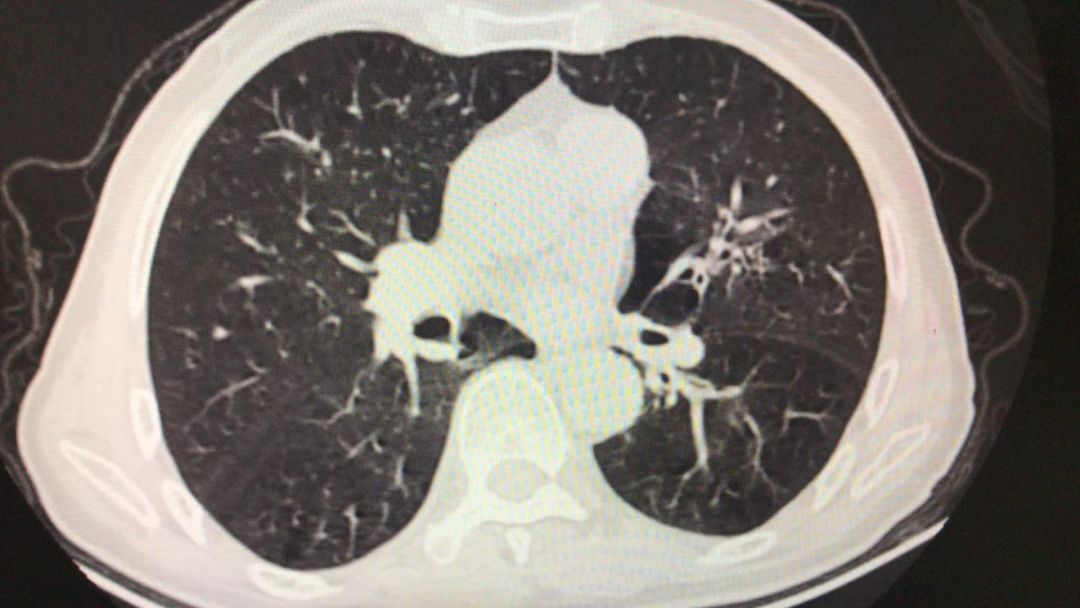

胸部CT平扫:两肺局限性肺气肿、肺大疱;两肺少许结节;右肺中叶及左肺上叶舌段慢性炎性病灶。